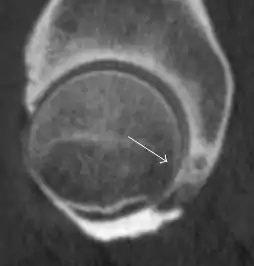

Intra-articular osseous causes of pain include several conditions: avascular necrosis (AVN), transient osteoporosis of the hip (TOH), tumors, and stress or insufficiency fractures. All these entities may present with a pattern of bone marrow edema characterized by decreased signal intensity on T1 weighted images and increased signal intensity on fluid sensitive sequences, such as fat saturated T2-weighted or STIR images. When there is no evidence of a focal lesion associated with the edema pattern, TOH is suspected. When a band of low intensity is seen inside the edematous area, the shape and length of this band become important. It is generally convex to the articular surface in the case of subchondral stress or insufficiency fractures, whereas it is concave, circumscribing all of the necrotic segment, in cases of AVN. When doubts do persist, gadolinium-enhanced MRI tends to show that the proximal portion beyond the band is enhanced in fractures but is not in AVN.[1]

MRI has been shown to have 100% sensitivity and specificity in prospective studies of occult hip fractures. These fractures were diagnosed by bone marrow edema and a low signal fracture line, mainly on T1 or T2 weighted images (Figure 10).[1]

Figure 10: